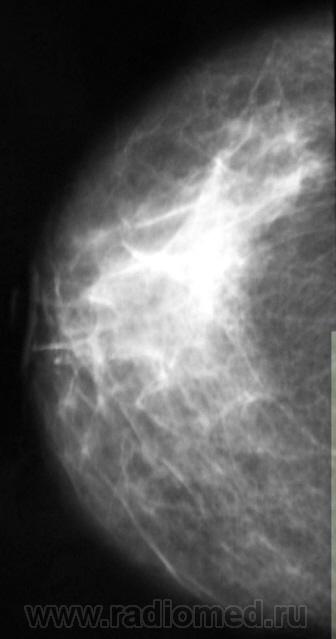

Сегодня проводились проф.осмотры. Наиболее интересные случаи я решил показать коллегам. Жалоб пациентки не предъявляли.

Сложно оринетироваться без маркировок, более плотный участок где он в косой проекции? Сохраняется, раходится на составляющие, Представлена одна железа, обе?

Иногда, в возможностях маммографии при наличии таких участков, по всей видимости, можно усомниться.

Валентин Львович, вы абсолютно правы, в таких ситуациях необходимо дополнять стандартное маммографическое исследование  проекциями под другими углами  и если такая картина сохраняется, делать УЗИ, направлять к онкологу.